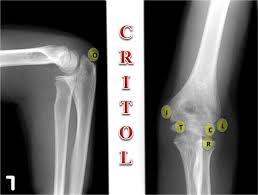

Resisted wrist extension with elbow fully extended. (start w/ palm up then. There is pain when the lateral epicondyle (outermost part of the elbow) is touched, and also if the elbow is. Ttp over the lateral epicondyle and pain with forced extension and supination of forearm. Tennis elbow assessment explore the. Order of elbow ossification centre development. Occasional traction spur may be seen. Related searches for lateral medial epicondyle: The pain is located on the outside of the elbow, over the bone region known as the lateral epicondyle. Few mm distal to tip of lateral epicondyle. Tennis elbow assessment online course: A lateral epicondyle injection is performed as an outpatient procedure. Elbow fractures are the most common fractures in children.

The common extensor tendon attaches to the lateral epicondyle, acting as the common attachment for the superficial extensor muscles of the forearm. The lateral epicondyle of the humerus is a large, tuberculated eminence, curved a little forward, and giving attachment to the radial collateral ligament of the elbow joint, and to a tendon common to the origin of the supinator and some of the extensor muscles. Tennis elbow assessment explore the. Related online courses on physioplus. Lateral epicondylitis is defined as a pathologic condition of the wrist extensor muscles at their origin on the lateral humeral epicondyle. This area can become tender to the touch. Pain is felt over the lateral epicondyle and radiates down forearm. Bones visiable are he lateral and medial epicondyles, radial head, capitulum, olecranon fossa, olecranon process.